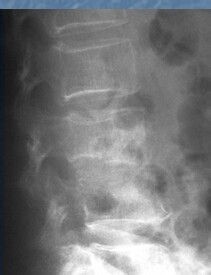

四:脊柱结核X线。